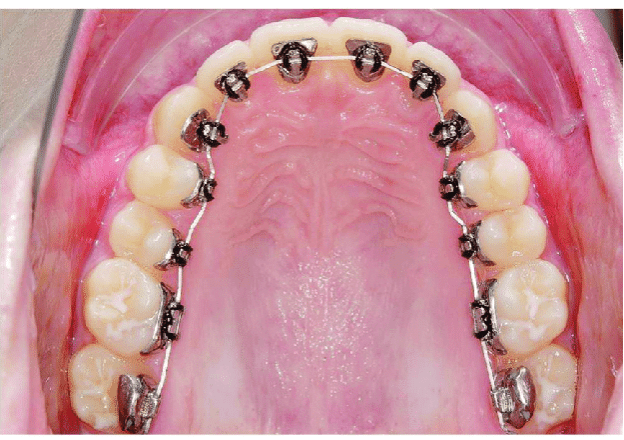

LINGUAL ORTHODONTIC APPLIANCES

Very aesthetic and precise. They are quite comfortable, But they produce fewer sores and chafing than other orthodontic appliances.The duration of lingual orthodontic treatment is usually longer compared to others.